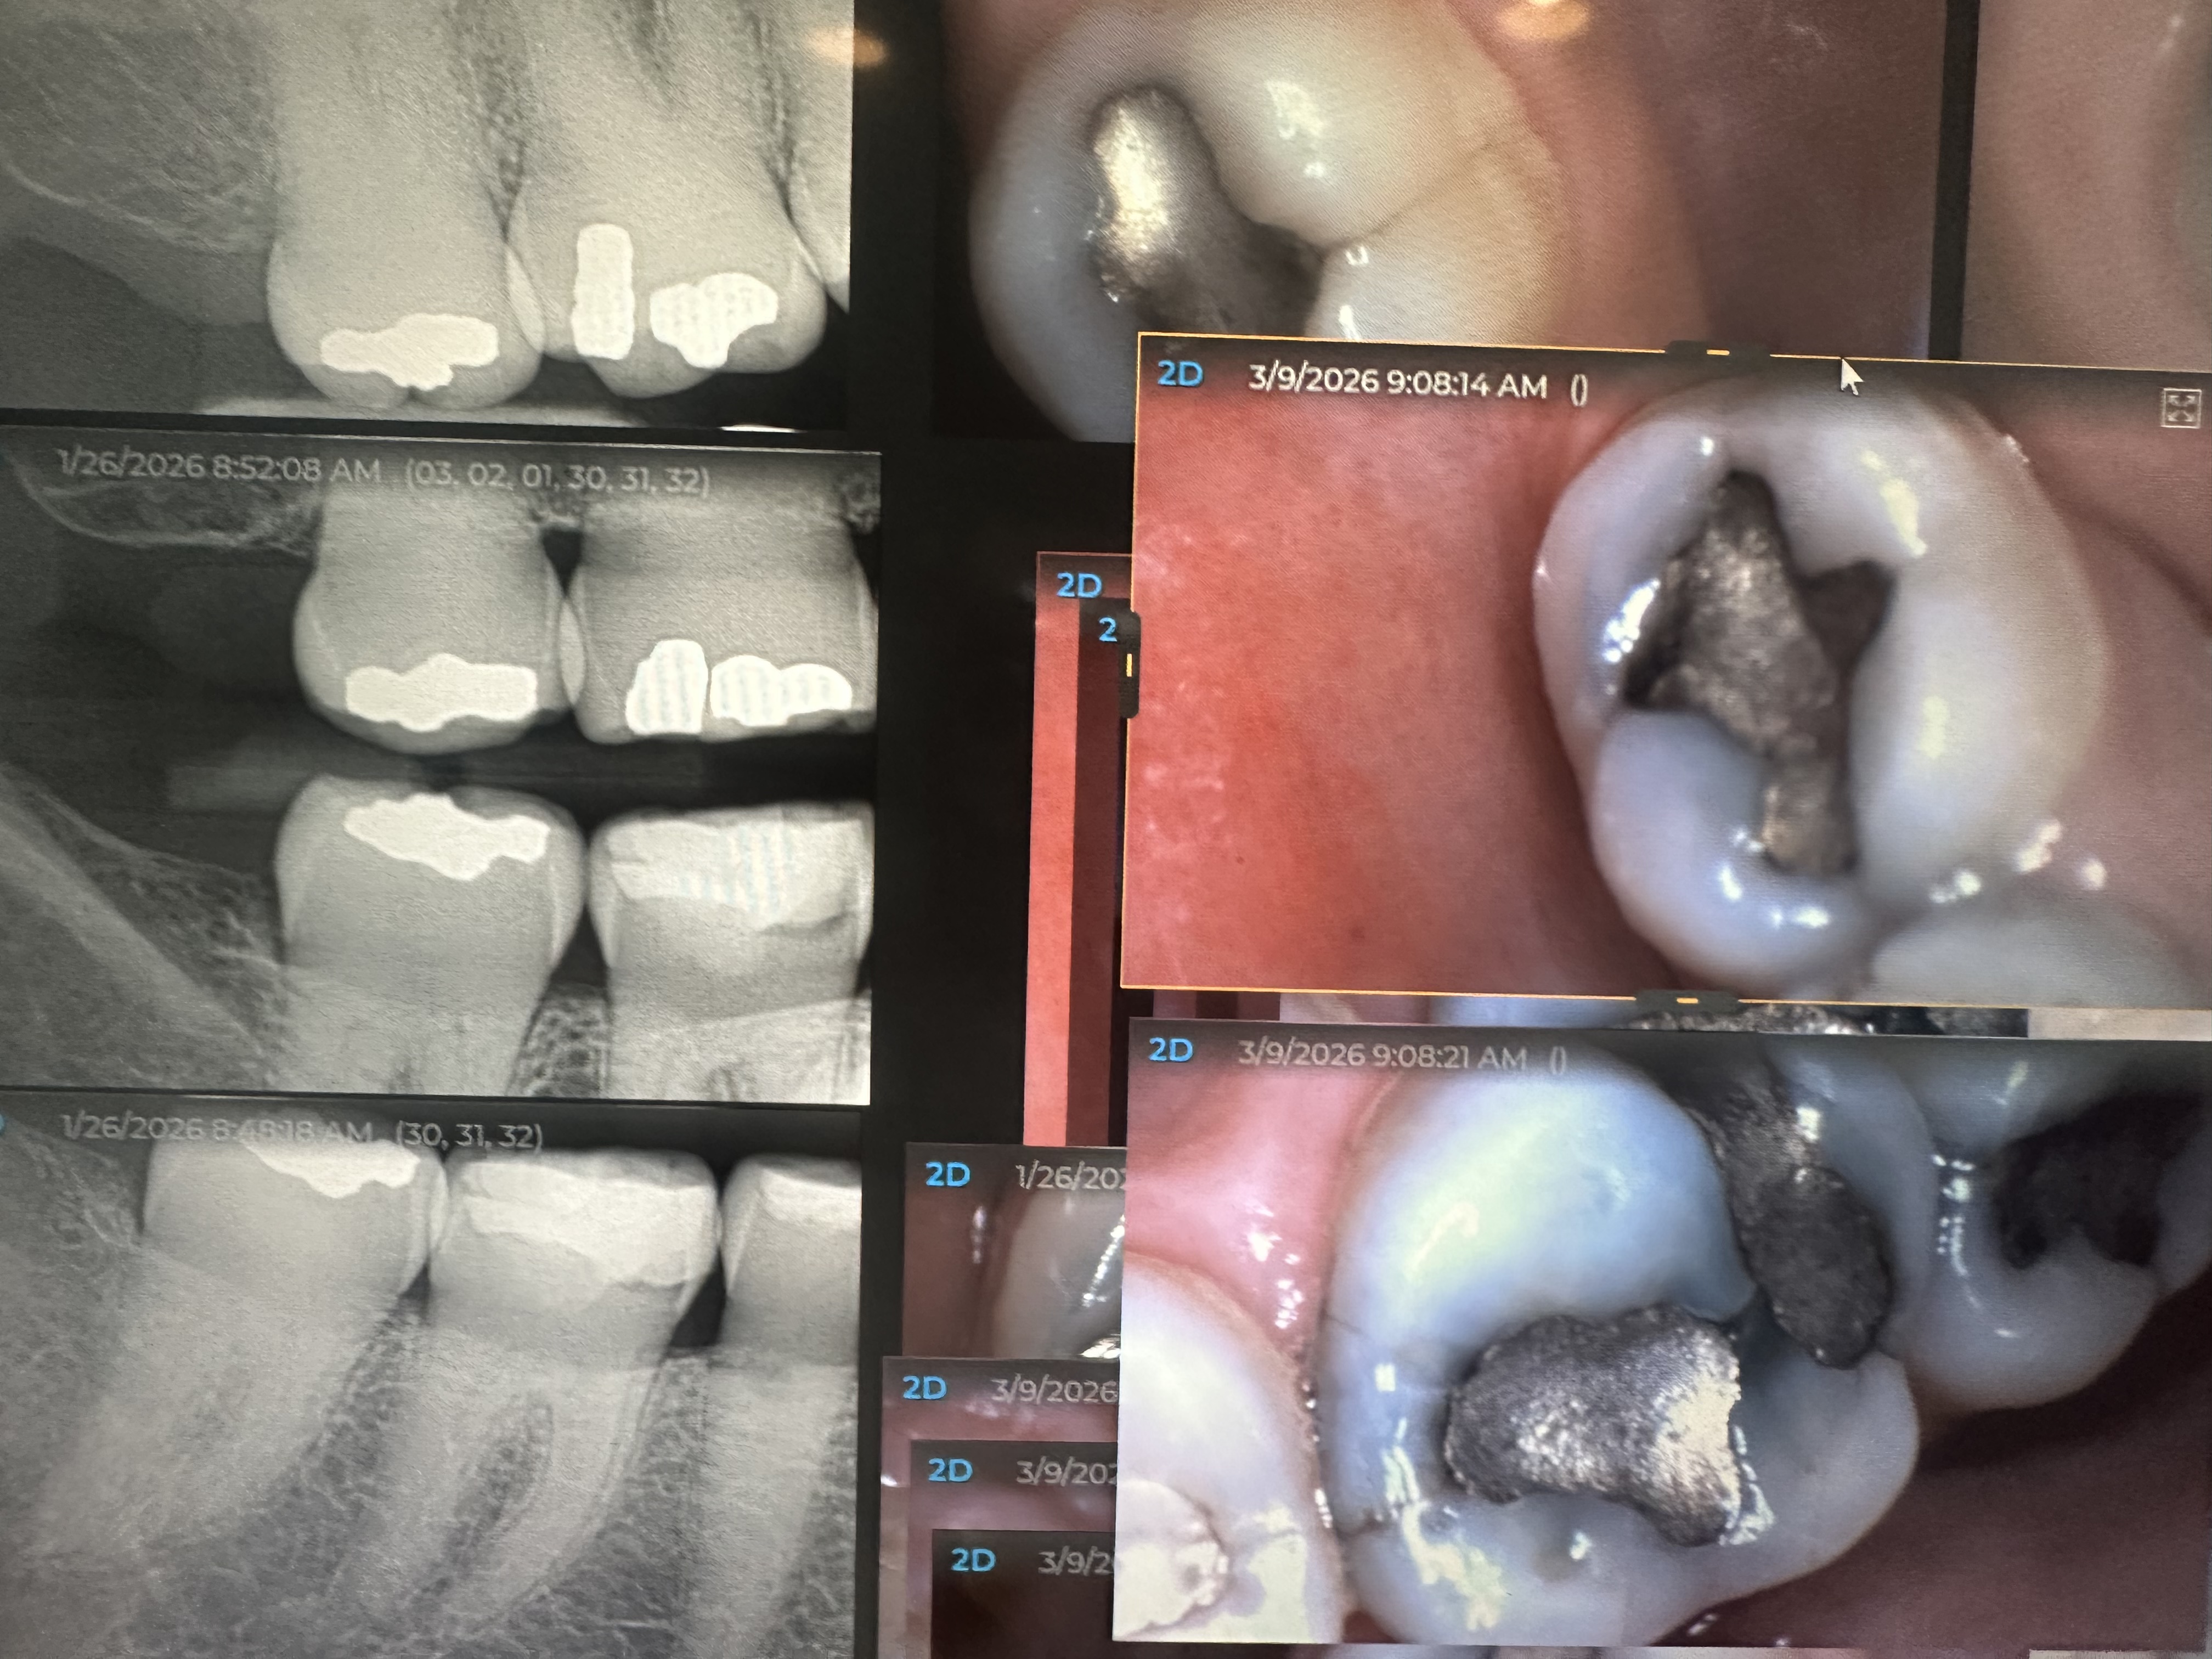

Mercury (amalgam) fillings have been used in dentistry for decades and are often referred to as “silver fillings.” What many patients are unaware of is that these restorations are composed of approximately fifty percent elemental mercury. Mercury is a known neurotoxin, and small amounts of vapor can be released from amalgam fillings over time, especially during chewing, grinding, or dental procedures that disturb the filling.

When mercury fillings are drilled or removed without proper precautions, mercury vapor and particles can be inhaled or absorbed through the oral tissues. While traditional dental removal methods may focus primarily on restoring the tooth, they often do not adequately address vapor control, airway protection, or environmental exposure.

Amalgam fillings are commonly called silver fillings because they cause a noticeable silver appearance in your teeth. This can be a big problem when the fillings are located at the front of the mouth, in teeth that are visible when you smile. This may make patients feel insecure about their smile, avoid taking photos, and take a toll on their self-esteem. Today, there are much more aesthetically pleasing filling alternatives.

Patients may have concerns that mercury is being released from their fillings every time they chew. If your fillings become damaged, broken, or fall out, this is an even bigger problem. This can expose you to toxic levels of mercury or even lead to mercury poisoning.